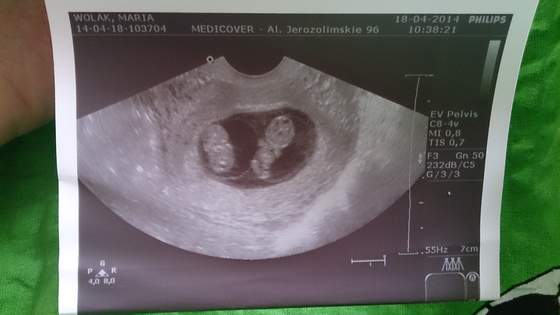

Znowu czuje dziewczyny z obu stron brzucha, tylko tamte dwa dni były takie nieszczęśliwe pod tym względem. Ciekawe jak teraz leżą wiercipiety.

Ja dowiedziałam sie o płci w 12tc i od tamtej pory nic sie nie zmieniło

Na usg4d jest duzo duzo za wcześnie, żaden lekarz nawet nie bedzie próbował Cie teraz na to naciągac